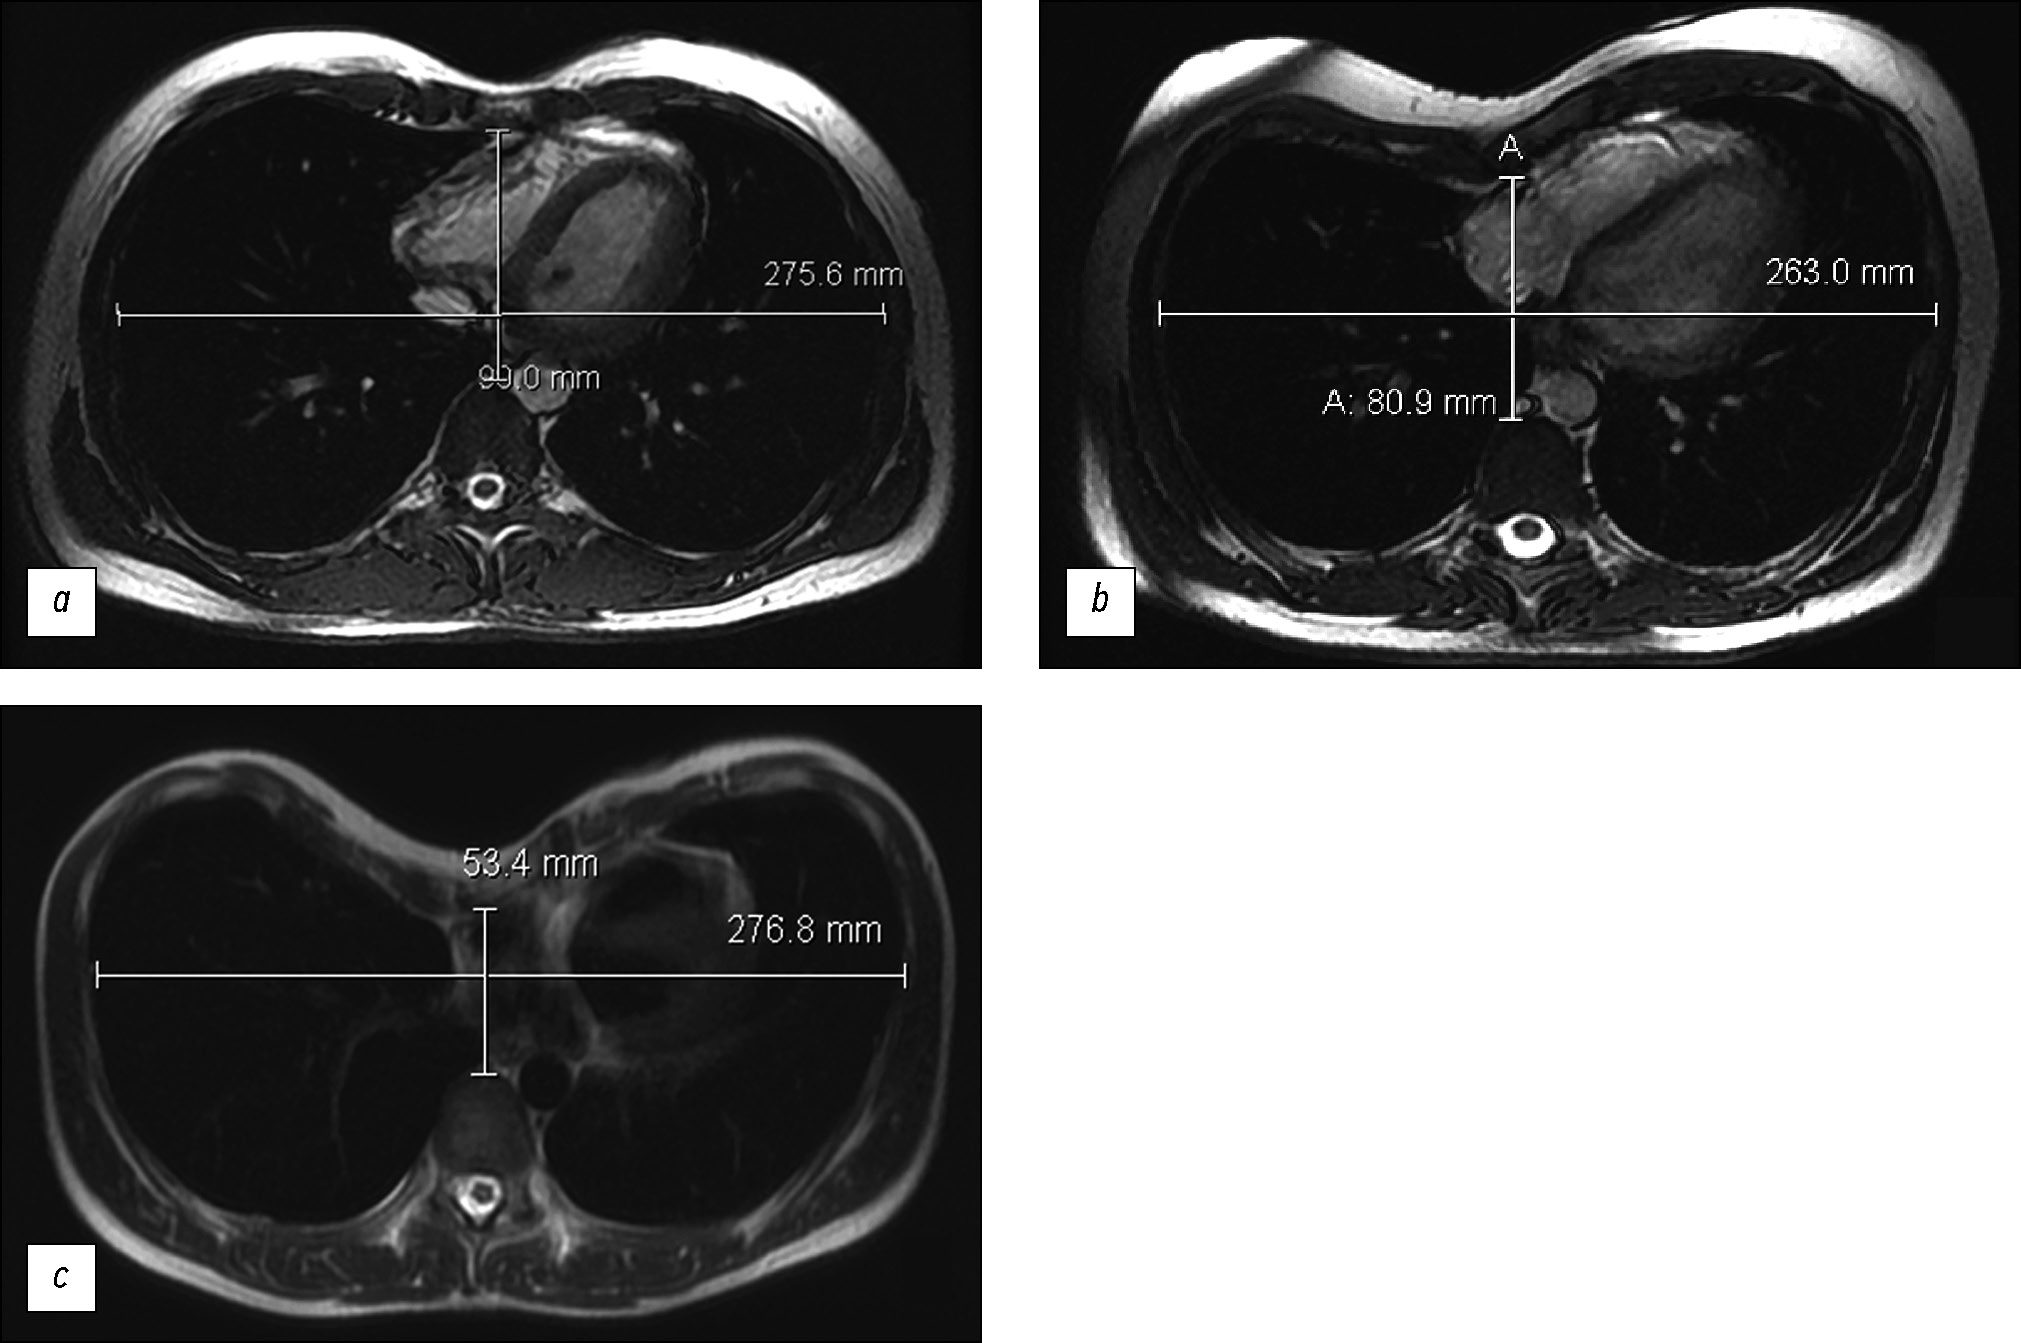

Comparison of the diagnostic accuracy of whole-body diffusion-weighted imaging and 18F-prostate-specific membrane antigen-1007 positron emission tomography combined with computed tomography for detecting bone metastases in prostate cancer

Abstract

BACKGROUND: The increasing availability of 18F-prostate-specific membrane antigen-1007 (18F-PSMA-1007) for prostate cancer staging highlighted its advantages, particularly its higher spatial resolution compared to analogs. Moreover, accumulating scientific data indicate an increase in false-positive findings, predominantly in bones, which may lead to unwarranted upstaging of the disease. Diffusion-weighted imaging may be used for the early detection of bone metastases.

AIM: This study aimed to assess and compare the diagnostic accuracy of whole-body 18F-PSMA-1007 positron emission tomography combined with computed tomography and whole-body and pelvic bone diffusion-weighted imaging in patients with prostate cancer.

METHODS: A retrospective single-center selective study was conducted. The imaging results of 119 patients with prostate cancer were divided into two groups: group 1 comprised 40 pairs of 18F-PSMA-1007 positron emission tomography combined with computed tomography and whole-body diffusion-weighted magnetic resonance imaging scans, and group 2 included 79 pairs of similar studies, with magnetic resonance imaging performed only for the pelvic bones. The diagnostic studies were performed at an inter-study interval ≤14 days. The metastatic bone lesions detected in different anatomical regions was counted using data from 18F-PSMA-1007 positron emission tomography combined with computed tomography and magnetic resonance imaging. Lesions were considered true positives if confirmed by additional magnetic resonance imaging pulse sequences and/or follow-up observation.

RESULTS: Whole-body diffusion-weighted imaging demonstrated higher specificity (58.1%) for detecting bone metastases than 18F-PSMA-1007 positron emission tomography combined with computed tomography (51.06%). However, its sensitivity was lower: 93.22% versus 97.55%.

CONCLUSION: Despite its advantages, 18F-PSMA-1007 positron emission tomography combined with computed tomography shows a high rate of false-positive bone findings. These are most commonly noted in the ribs, vertebrae, and pelvic bones. Suspicious bone lesions should be further evaluated to avoid unjustified disease upstaging. Thus, whole-body magnetic resonance imaging with diffusion-weighted sequences and selective fat signal suppression can be used.

239-250